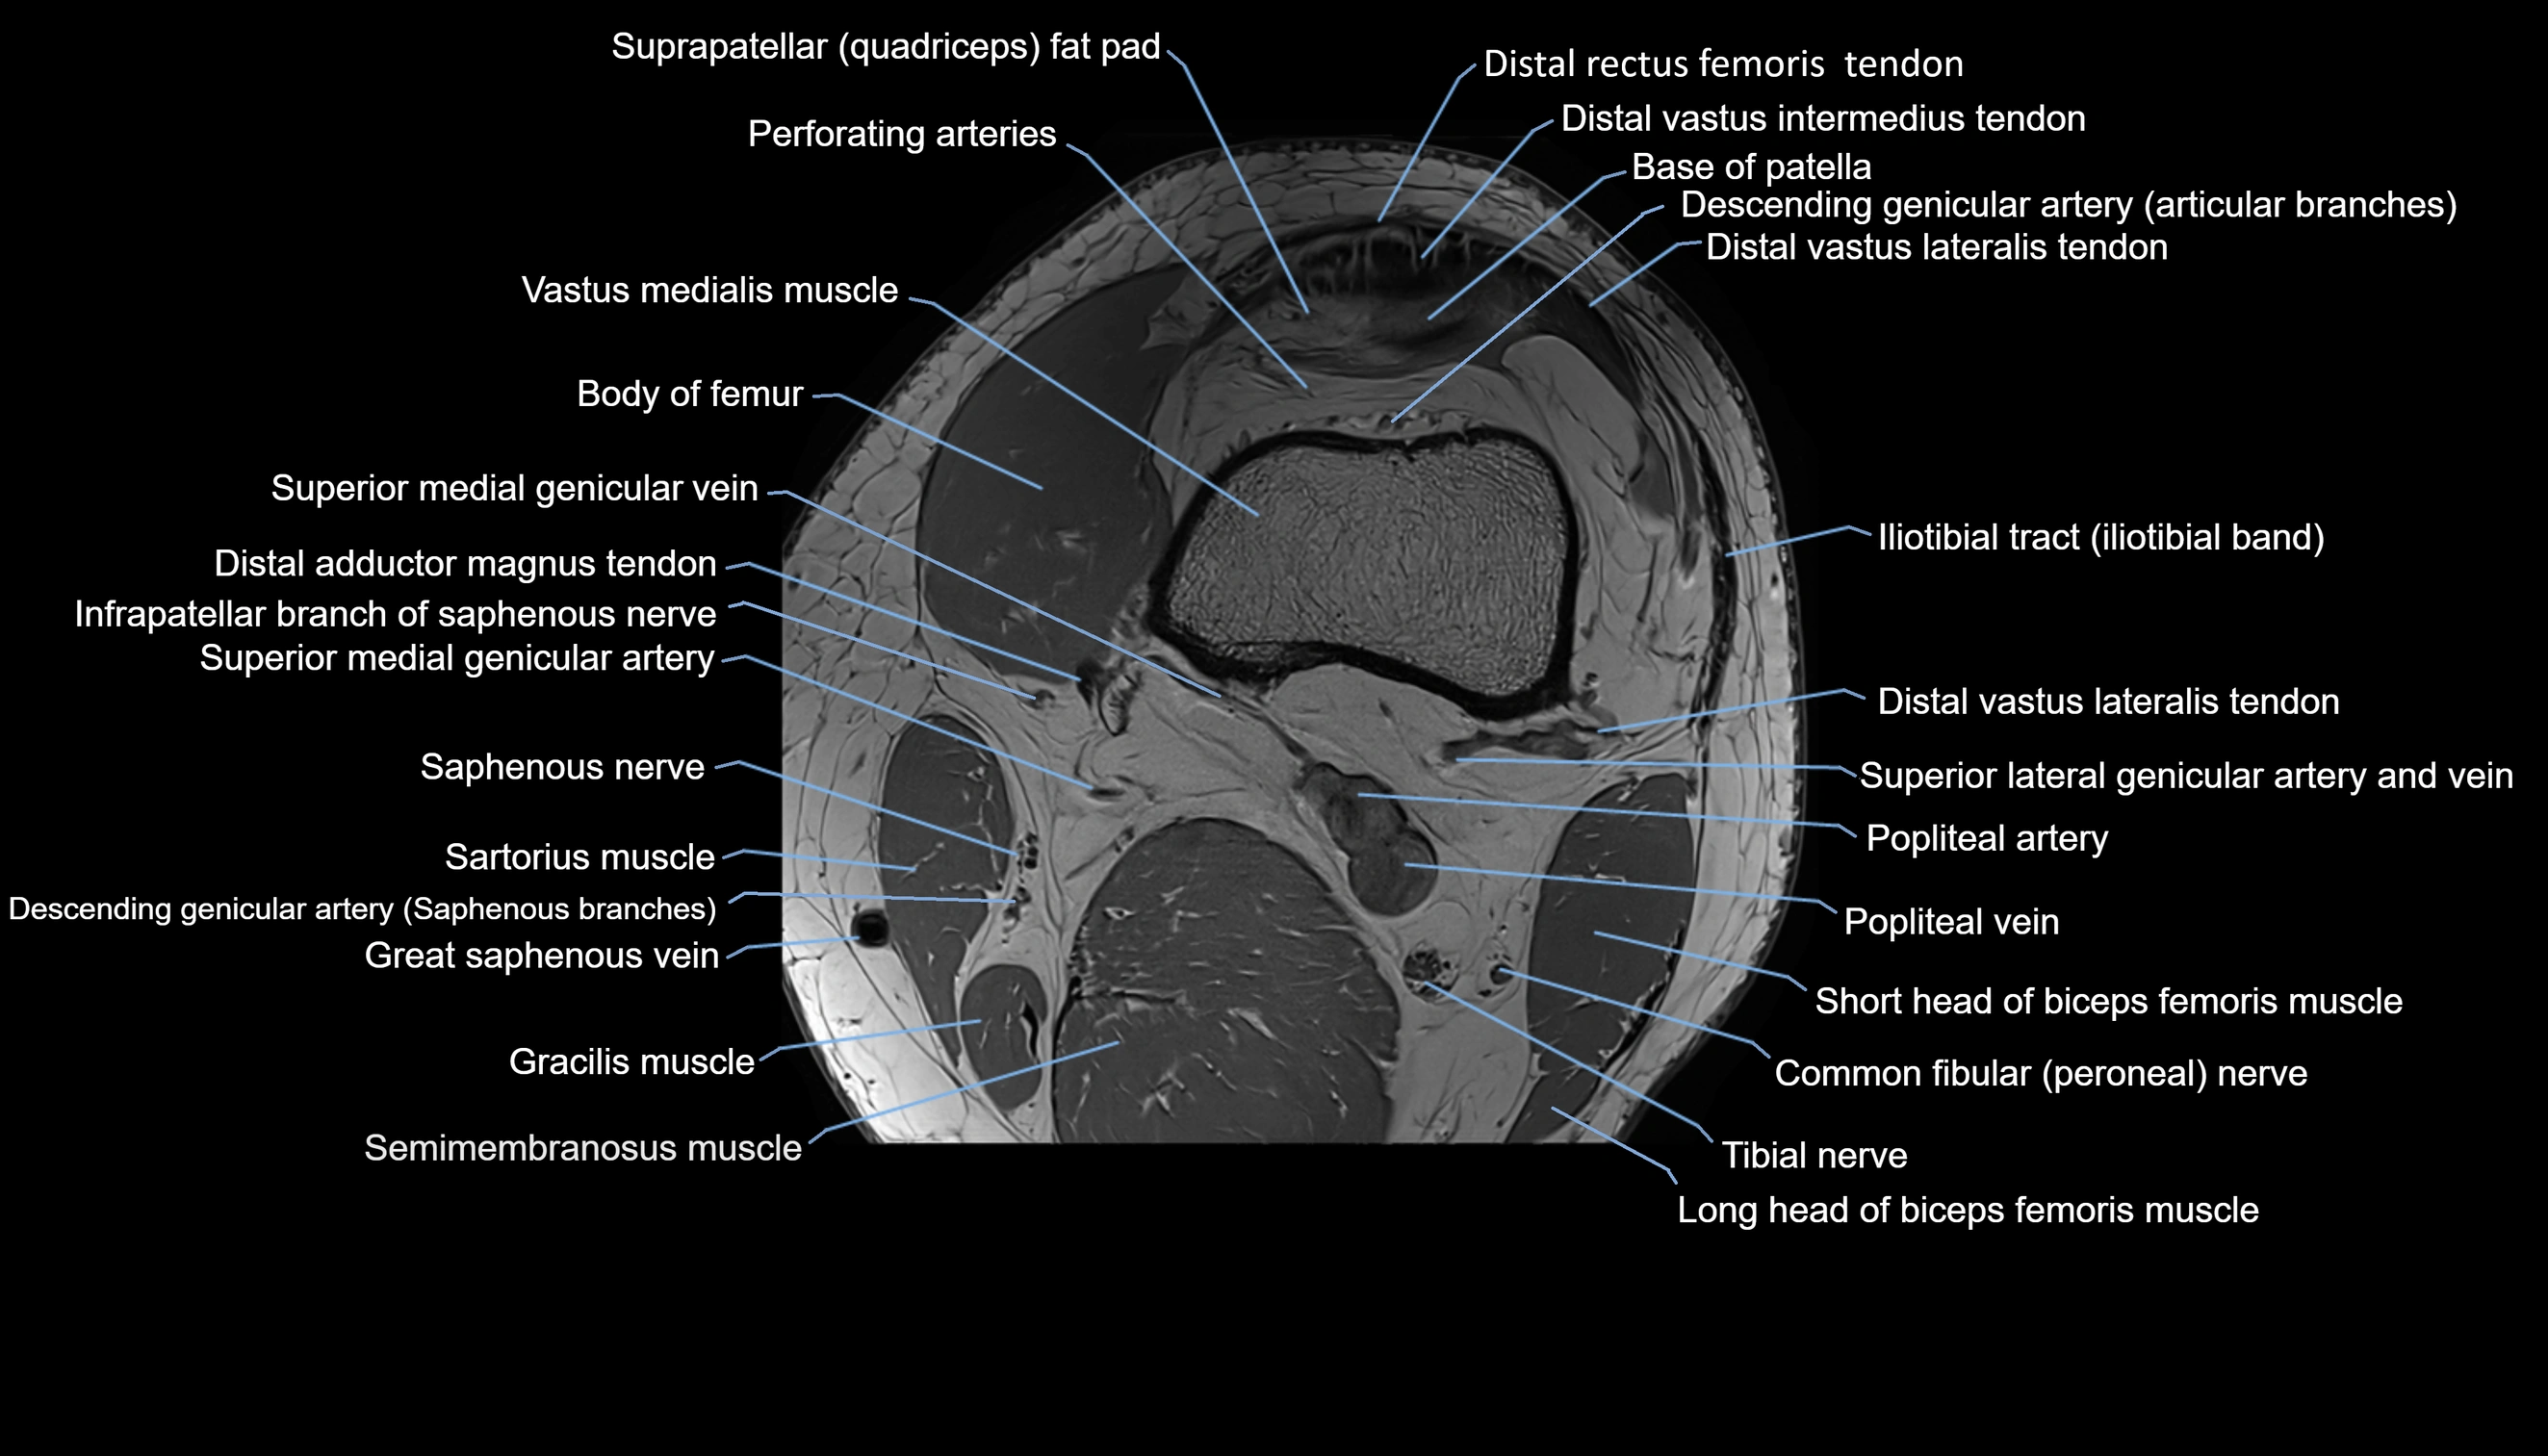

- Knee Joint